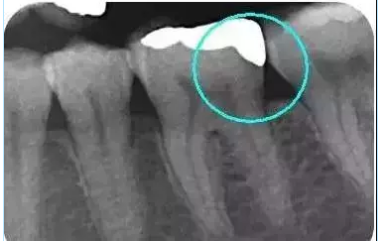

從下面這張X線中可以看出,嵌體遠中邊緣沒有懸突,與牙體邊緣密合相接。